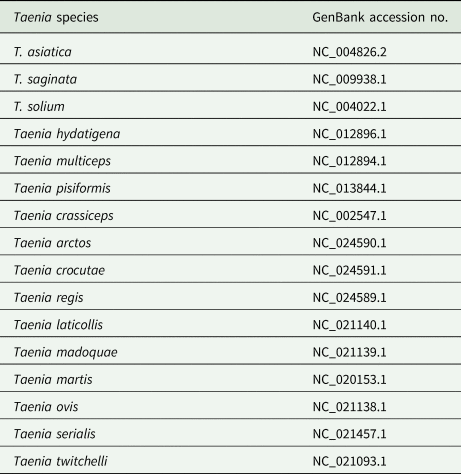

The routine laboratory blood tests, including eosinophil and lymphocyte count, were completely normal apart from the elevated inflammation markers (C-reactive protein and neutrophil count). Schistosomes, Clonorchis sinensis, Echinococcus granulosus and Toxoplasma gondii antibodies were negative in his serum, as were Cryptococcus capsular antigen and next-generation sequencing results from cerebrospinal fluid. Multiple intracranial nodules affecting the supratentorial and infratentorial cerebral parenchyma were shown in detail on CT and MRI of the head, indicating possible intracranial parasitic infection (Fig. 1). Ultrasound scan confirmed the presence of 2 palpable and soft masses located in muscles, which were approximately 19 × 8 × 15 mm3 under the right chest wall and 26 × 10 × 19 mm3 under the right midaxillary line (Fig. 2). A subsequent biopsy of the mass (Fig. 3) showed larval-like tissue, peripheral fibrous tissue hyperplasia, lymphocytic infiltration and hyaline degeneration. The patient was probably diagnosed with taeniasis and cysticercosis and treated with oral albendazole (400 mg, twice daily) over 2 weeks. Hydrocortisone 50 mg was provided 2 days after the first albendazole treatment to counteract any potential negative effects on the central nervous system. After only 2 days of this antiparasitic treatment, the adult tapeworm was eliminated through the patient's feces (Fig. 3). When compared with the first MRI (half a month before antiparasitic treatment), the second MRI (half a month after antiparasitic treatment) demonstrated a slightly smaller focus (Fig. 1). The headache and vomiting resolved, and the patient remained symptom free over a 3-month follow-up period.

Fig. 2. Ultrasound scan shows hypoechoic mass containing cysticercus with calcification in the muscles of (A, B) right anterior thoracic wall (19 × 8 × 15 mm3) and (C, D) right midaxillary line (26 × 10 × 19 mm3).